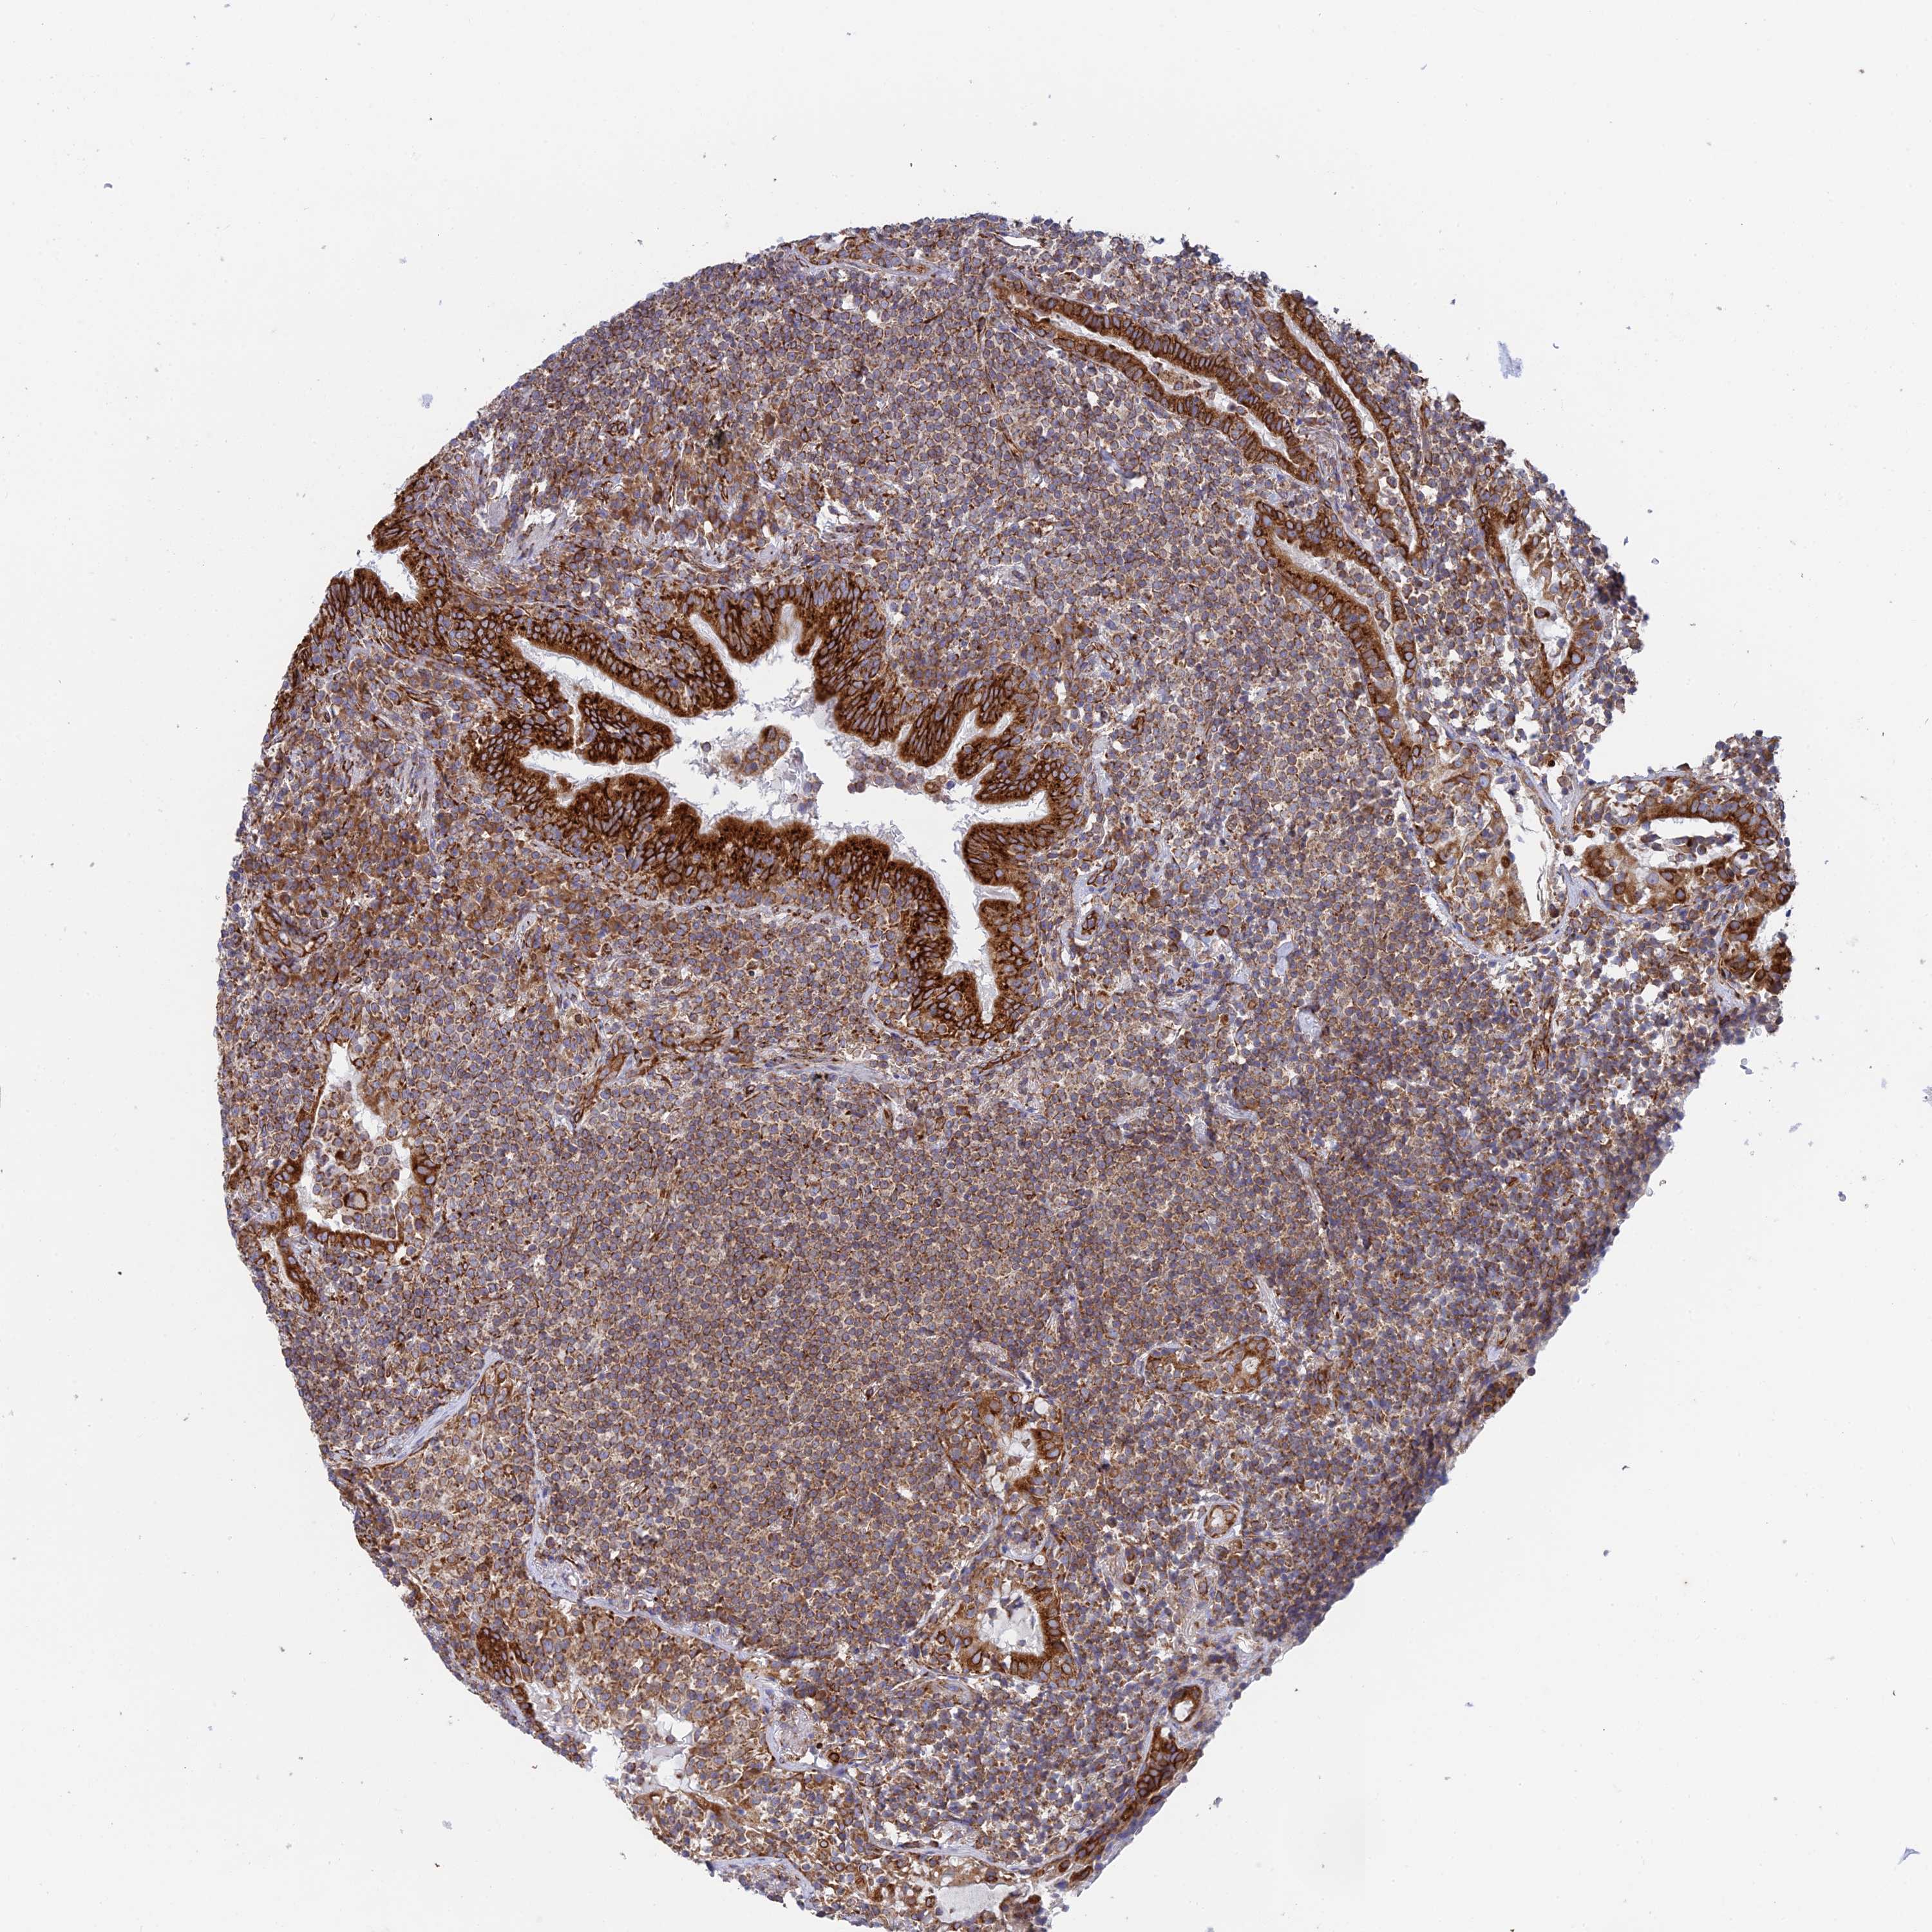

CANCER LYMPHOMA Show tissue menu

LYMPHOMA - Protein expressioni

A mouse-over function shows sample information and annotation data. Click on an image to view it in a full screen mode. Samples can be filtered based on level of antibody staining by selecting one or several of the following categories: high, medium, low and not detected. The assay and annotation is described here.

Antibody stainingi

Antibody staining in the annotated cell types in the current human tissue is reported as not detected, low, medium, or high, based on conventional immunohistochemistry profiling in selected tissues. This score is based on the combination of the staining intensity and fraction of stained cells.

Each image is clickable and will lead to virtual microscopy that enables deeper exploration of all samples and also displays staining intensity scores, fraction scores and subcellular localization as well as patient and tissue information for each sample.

Antibody HPA043648

Staining

High

Intensity

Strong

Quantity

>75%

Location

Nuclear

Hodgkin's disease, NOS

Malignant lymphoma, non-Hodgkin's type, High grade

Malignant lymphoma, non-Hodgkin's type, Low grade